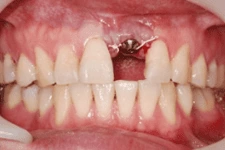

3. 即拔即種

打破傳統即拔即種(又叫立即植牙),拔牙後立刻植牙。患者可在拔牙後立即植入人工植體,並立刻裝戴假牙。讓你治療當天就能擁有美觀的門面。

我們在植牙領域的突破,克服患者對手術的恐懼,也同時幫助患者告別了缺牙的痛苦,讓患者重新擁有一口完美的牙齒。

↑ 治療後:微創立即植牙恢復美麗外觀